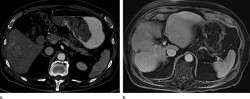

El Hospital Santa Clotilde de Santander ha inaugurado este viernes un nuevo servicio de diagnóstico por imagen, único en Cantabria, con el que añade a sus instalaciones la última tecnología en imagen médica a través de inteligencia artificial (IA), y que también incluye una unidad específica para la mujer.